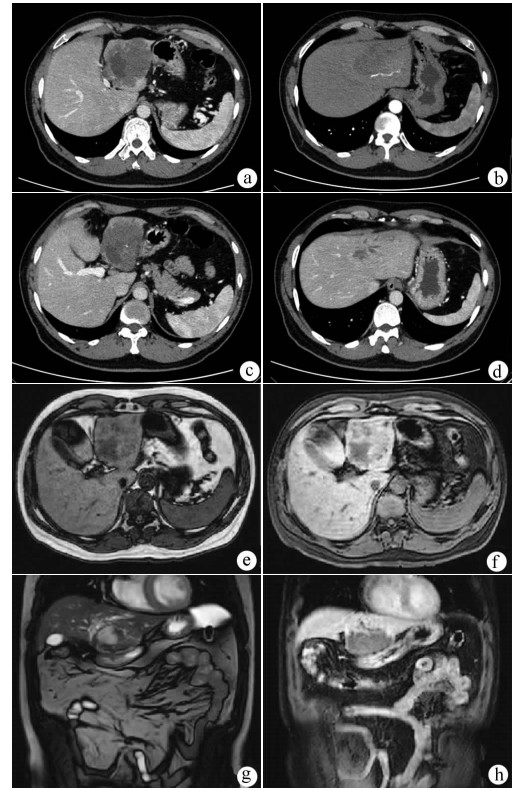

Hepatic alveolar echinococcosis misdiagnosed as intrahepatic cholangiocarcinoma: A case report

Kai ZHAO, Zhixin WANG, Shengbao WEN, Haijiu WANG, Haining FAN, Li REN

2021, 37(5): 1183-1185. DOI: 10.3969/j.issn.1001-5256.2021.05.042

Abstract(1037) HTML (359) PDF (2157KB)(63)

Abstract: